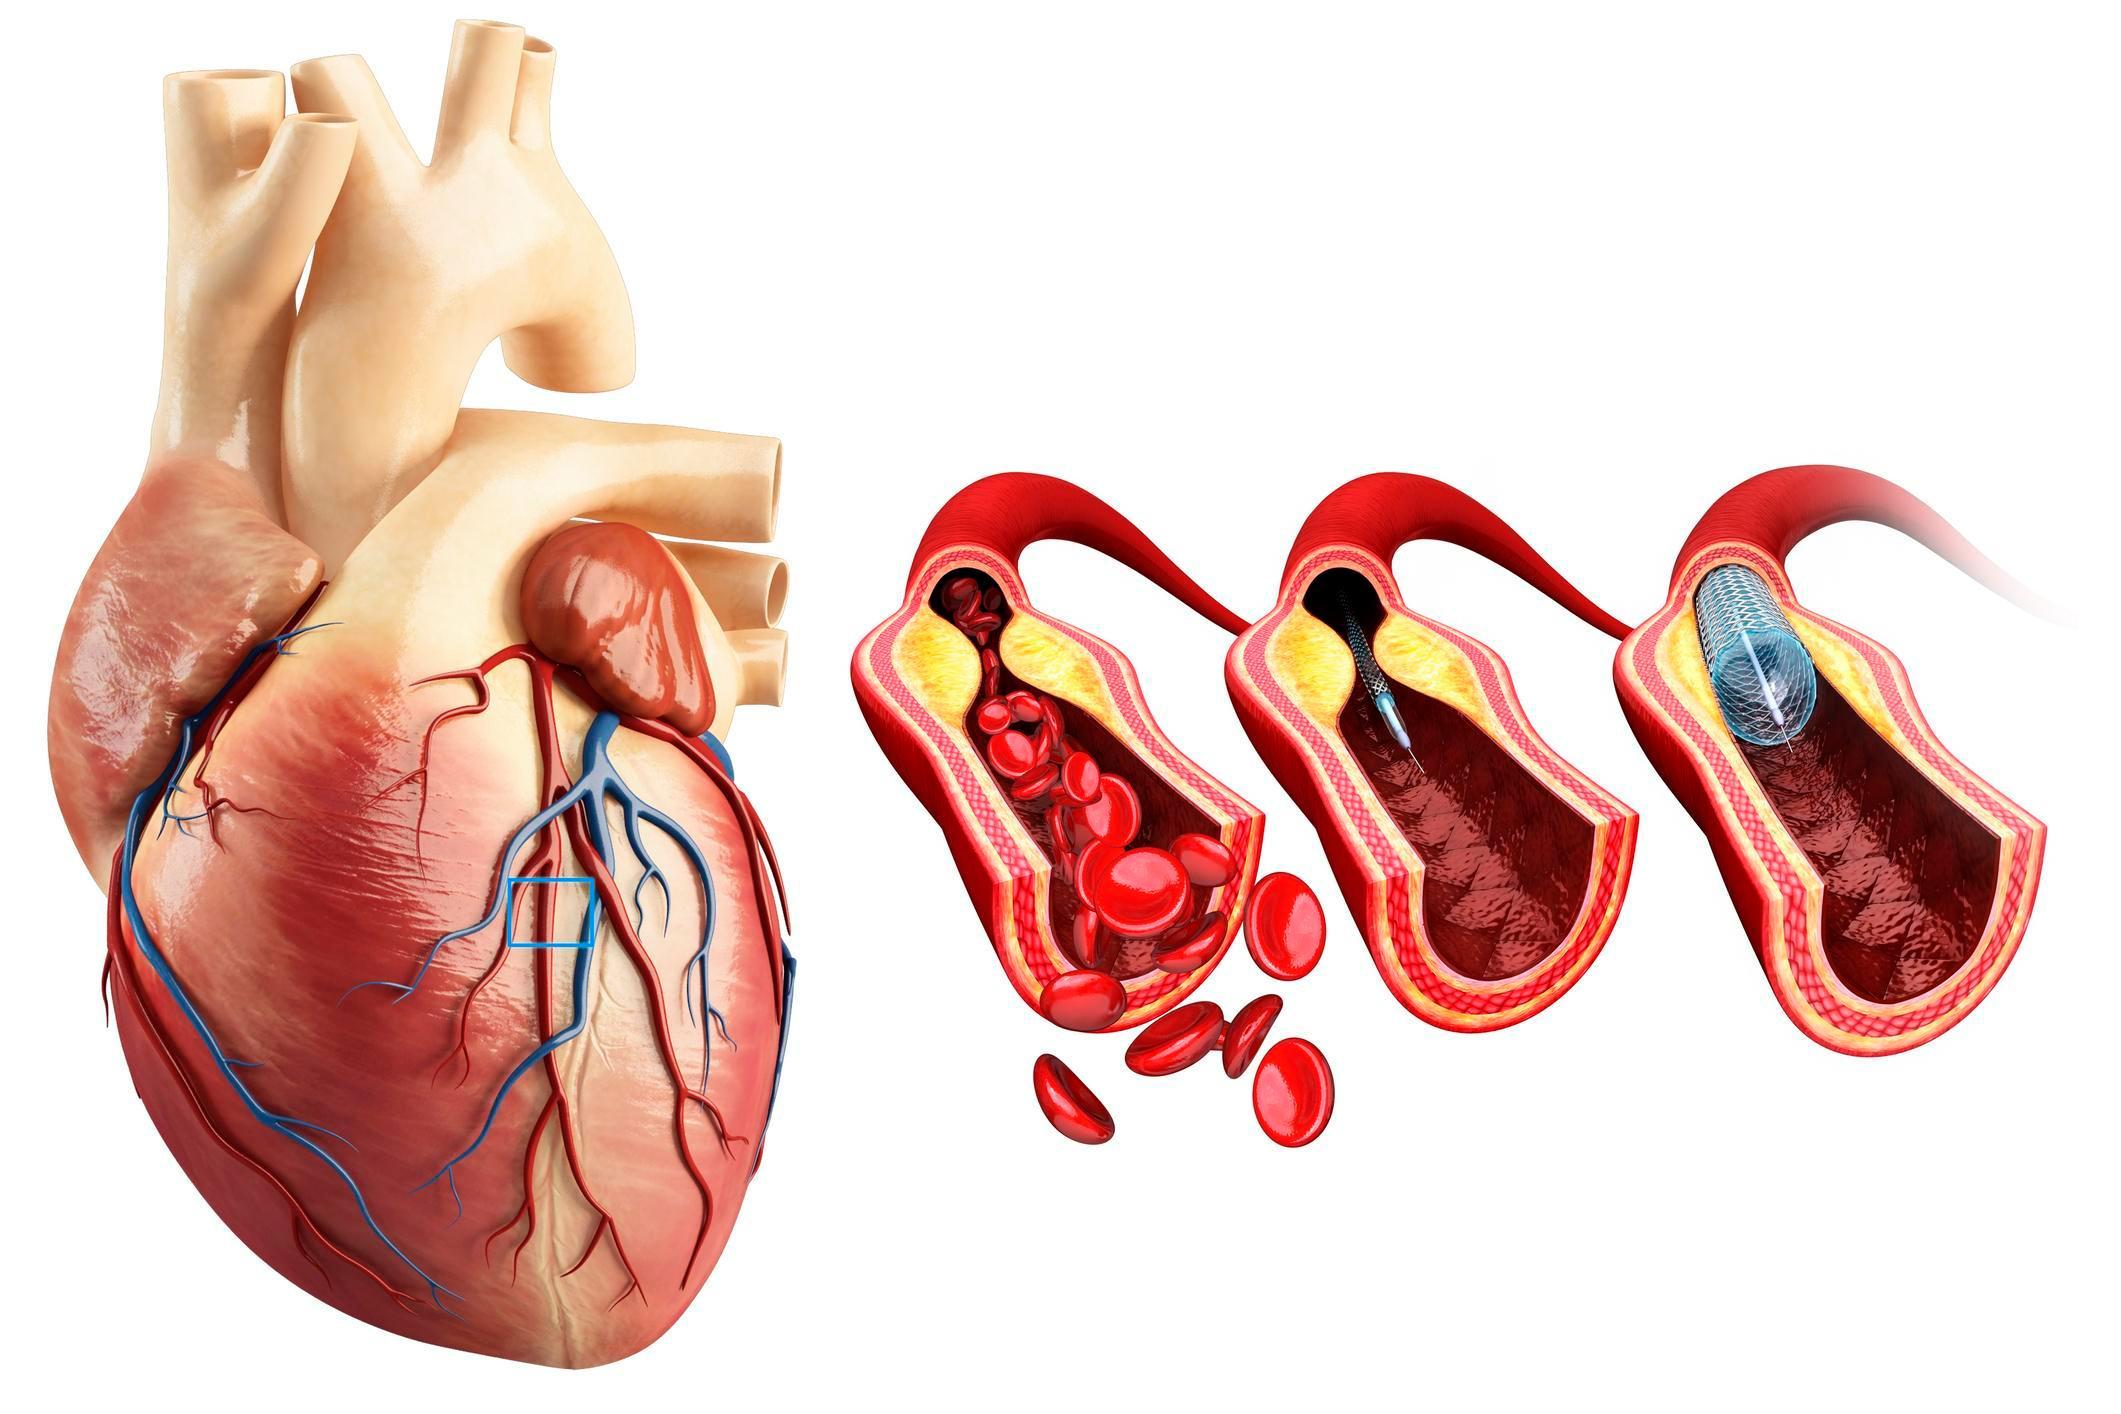

Procesele care stau la baza cardiopatiei ischemice sunt în principal legate de reducerea fluxului sanguin coronarian; ateroscleroza coronariană poate produce îngustări progresive ale arterelor și favorizează formarea placilor care pot ulceriza sau tromboza, reducând aportul de oxigen către mușchiul cardiac. În anumite situații, spasmul arterial sau disfuncţia microvasculară pot contribui la ischemie chiar în lipsa unor stenoze majore, iar dezechilibrele între cererea și oferta de oxigen (de exemplu în anemia severă sau la suprasolicitare) pot agrava tabloul clinic.

Terapia farmacologică rămâne un pilon central în managementul cardiopatiei ischemice și, în funcție de contextul clinic, poate include clase de medicamente precum antiagregante plachetare, statine, beta-blocante, inhibitori ai enzimei de conversie sau antagoniști ai receptorilor angiotensinei, precum și nitrați sau blocante ale canalelor de calciu, iar în situații selecte pot fi necesare și anticoagulante. Aceste tratamente pot ameliora simptomele de angină, pot contribui la stabilizarea leziunilor aterosclerotice și pot reduce riscul evenimentelor cardiovasculare; alegerea, combinația și monitorizarea lor trebuie adaptate individual de echipa medicală, cu atenție la efecte adverse și interacțiuni.

Intervențiile revascularizante, precum angioplastia coronariană cu stent sau bypass-ul coronarian, pot fi indicate atunci când anatomia coronariană și severitatea simptomelor justifică procedura și pot îmbunătăți fluxul sanguin și calitatea vieții în anumite cazuri. Programele de reabilitare cardiacă, educația pacientului și controlul strict al factorilor de risc cardiovasculare – renunțarea la fumat, activitate fizică adaptată, alimentație sănătoasă și optimizarea controlului tensiunii arteriale și glicemiei – pot susține rezultatele pe termen lung. Tratamentul trebuie adaptat individual și coordonat de un specialist pentru a echilibra beneficiile și riscurile.